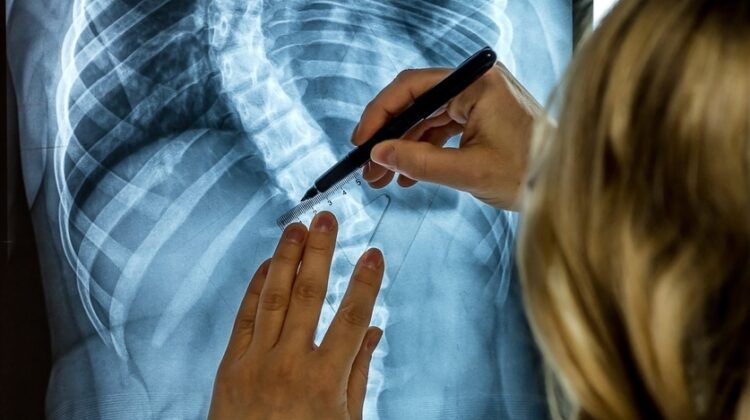

يمكن للأهل ملاحظة بعض العلامات البسيطة، مثل عدم تساوي الكتفين، بروز أحد جانبي الظهر عند الانحناء للأمام، اختلاف مستوى الحوض، أو ميل الجذع إلى أحد الجانبين. عند ظهور أي من هذه العلامات، يجب استشارة الطبيب الذي يؤكد التشخيص باستخدام الأشعة وقياس زاوية الانحناء.